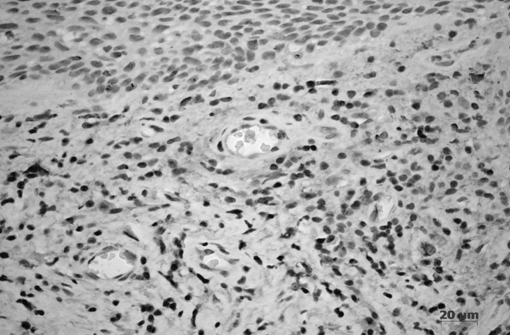

Противовоспалительный цитокин TGF-b1 экспрессировался клетками соединительной ткани. Причем, интенсивность выделения напрямую зависела от степени повреждения и от стадии воспаления. Так, наименьшее его количество выявлялось при хроническом гингивите в начальной стадии заболевания в экссудативную стадию воспаления и в основном клетками макрофагального ряда (рис. 4), а наиболее интенсивно трансформирующий фактор роста — b1 секретировался в пролиферативной стадии воспаления следующими клетками: макрофагами, плазмоцитами, фибробластами и мезенхимными клетками. Причем данный цитокин выявлялся как эндогенно, так и экзогенно (рис. 5).

Рис. 4. Хронический катаральный гингивит. Стадия экссудации. Экспрессия TGF-b1 макрофагами в строме собственной пластинки десны. Иммуногистохимическая реакция на TGF-b1. Докраска гематоксилином.

Рис. 5. Хронический генерализованный катаральный гингивит. Стадия пролиферации. Экспрессия TGF-b1 в строме собственной пластинки десны. Иммуногистохимическая реакция на TGF-b1. Докраска гематоксилином.

При иммуногистохимическом исследовании c применением TGF-b1 было выявлено, что при хроническом генерализованном пародонтите легкой степени заболевания цитокин выявлялся в меньшей степени и только макрофагами, а при средней степени его количество значительно увеличивалось соответственно тяжести повреждения за счет инфильтрирующих клеток (рис. 6, 7). В круговой связке зуба выраженность экспрессии прямо пропорционально коррелировала с тяжестью заболевания.

Рис. 6. Хронический локализованный пародонтит легкой степени тяжести. Экспрессия TGF-b1 макрофагами в собственной пластинке десны Иммуногистохимическая реакция на TGF-b1. Докраска гематоксилином.

Рис. 7. Хронический локализованный пародонтит средней степени тяжести. Экспрессия TGF-b1 клетками соединительной ткани: макрофагами, фибробластами, лимфоцитами, плазмоцитами. Иммуногистохимическая реакция на TGF-b1. Докраска гематоксилином.